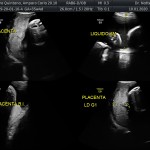

Los objetivos más importantes de esta ecografía son la evaluación de:

- El escenario Gravídico: Placenta, Liquido y Anexos.